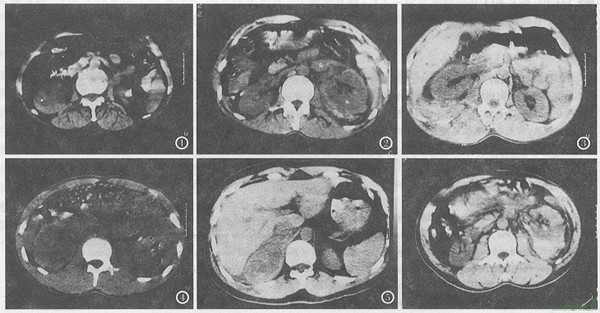

长期吸食海洛因对肾脏的影响有:急性肾功能衰竭,少数海洛因依赖者在注射海洛因后出现伴有肌球蛋白尿的急性肌病,临床上表现为肌肉触痛、水肿和极度的全身虚弱感,这些病人的血清球蛋白、尿肌球蛋白浓度高。这类病人中有60%会发生急性肾功能衰竭。

在出现急性肾小球肾炎的综合征患者,做肾脏病理检时,常常会出现免疫球蛋白和补体沉积。此时,细菌的细胞壁抗原及相应抗体可能通过旁路途径激活补体导致肾小球损伤。少数情况下,用于治疗这种细菌性心内膜炎的抗生素又可导致急性药物性小管间质性肾炎。因此,海洛因成瘾引起的肾功能衰竭往往是多种肾损害的综合结果。

研究表明,“白粉”中的吗啡可以通过多种途径诱导肾脏损伤的发生:诱导肾小球系膜细胞的增殖,刺激系膜细胞基质的合成;降低系膜细胞金属蛋白酶的活性;促进免疫复合物在肾小球系膜区的积聚;降低单个核吞噬细胞系统的吞噬功能;刺激系膜细胞超氧化物的形成;诱导单个核细胞移行至系膜区。

吗啡在低浓度时可以通过调节早期生长相关基因mRNA的表达促进肾脏成纤维细胞增殖,而在高浓度时通过促进p53的产生,诱导肾脏成纤维细胞的凋亡。